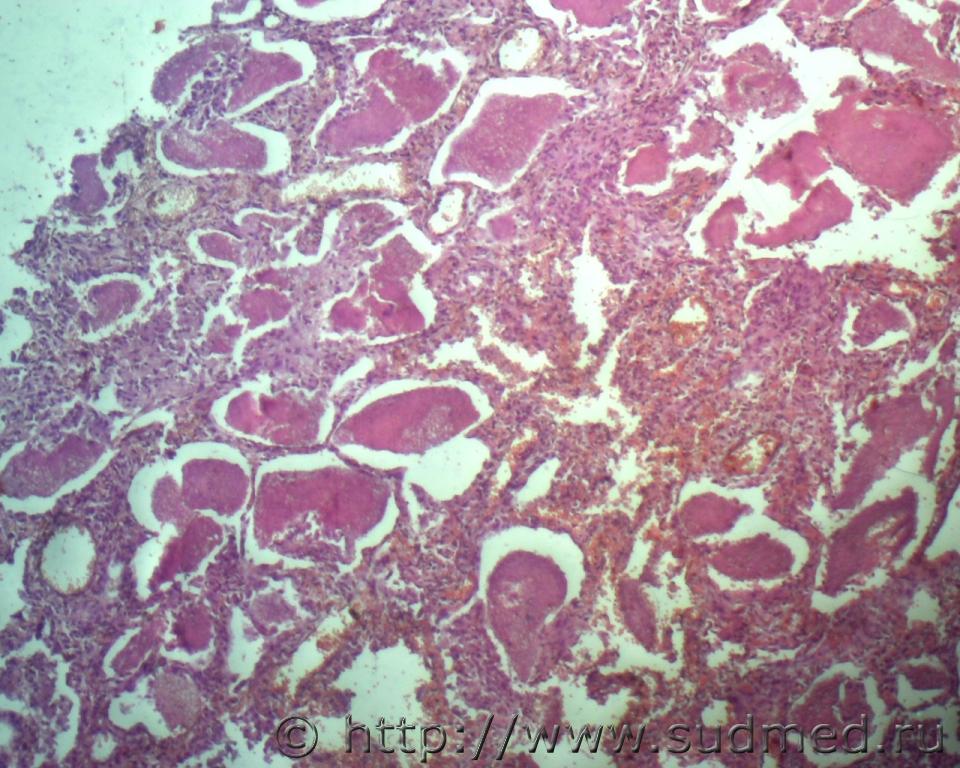

Реканализация тромба артерии лёгкого.